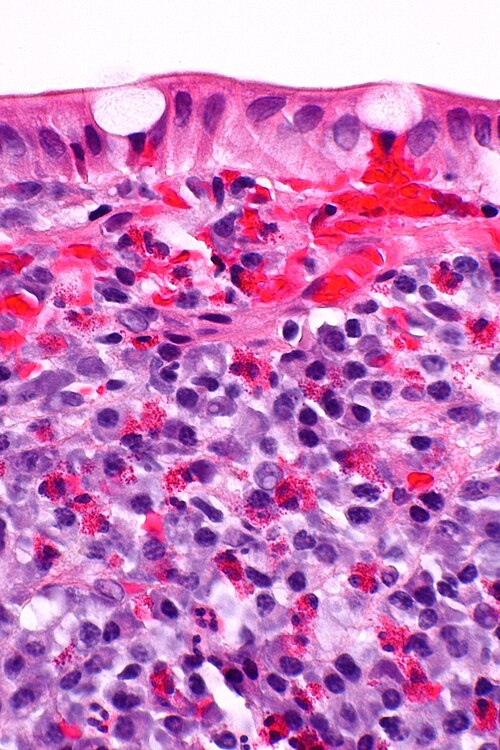

Eosinophils in eosinophilic colitis. (WC)

Features:

- Bilobed nucleus.

- Granular eosinophilic cytoplasm.

- Paneth cells - for intraepithelial eosinophils.

- Eosinophils have smaller (~1/2) more intensely red granules.